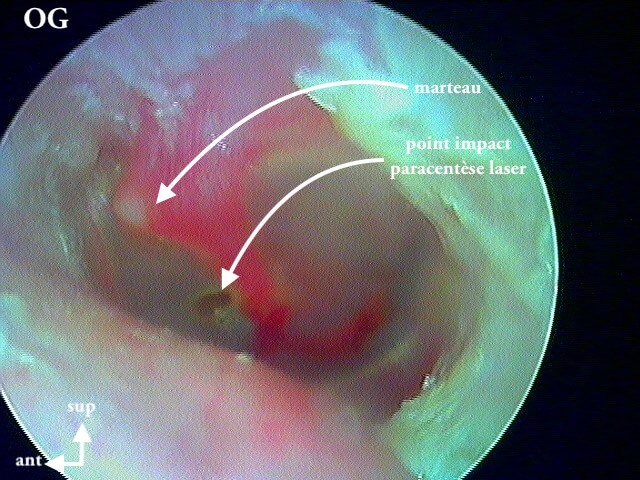

Pour comprendre la paracentèse, ici au laser diode sous A/L au cabinet:

Et la mise en place d'aérateur de type T-tube ici: